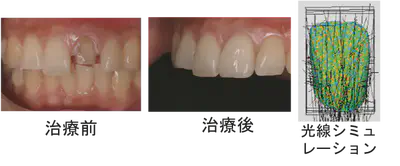

患者の口腔内の審美性に対する要求が高まっています。特に前歯部においては単に機能を回復するだけでなく、天然歯に近似した色調や光の透過性を有する修復治療が求められています。そこで、各種歯冠修復材料や歯の組織の光学特性を分析し光学的シミュレーションを行うことで、天然歯や歯冠修復物における光の振る舞いを可視化し、解析します。